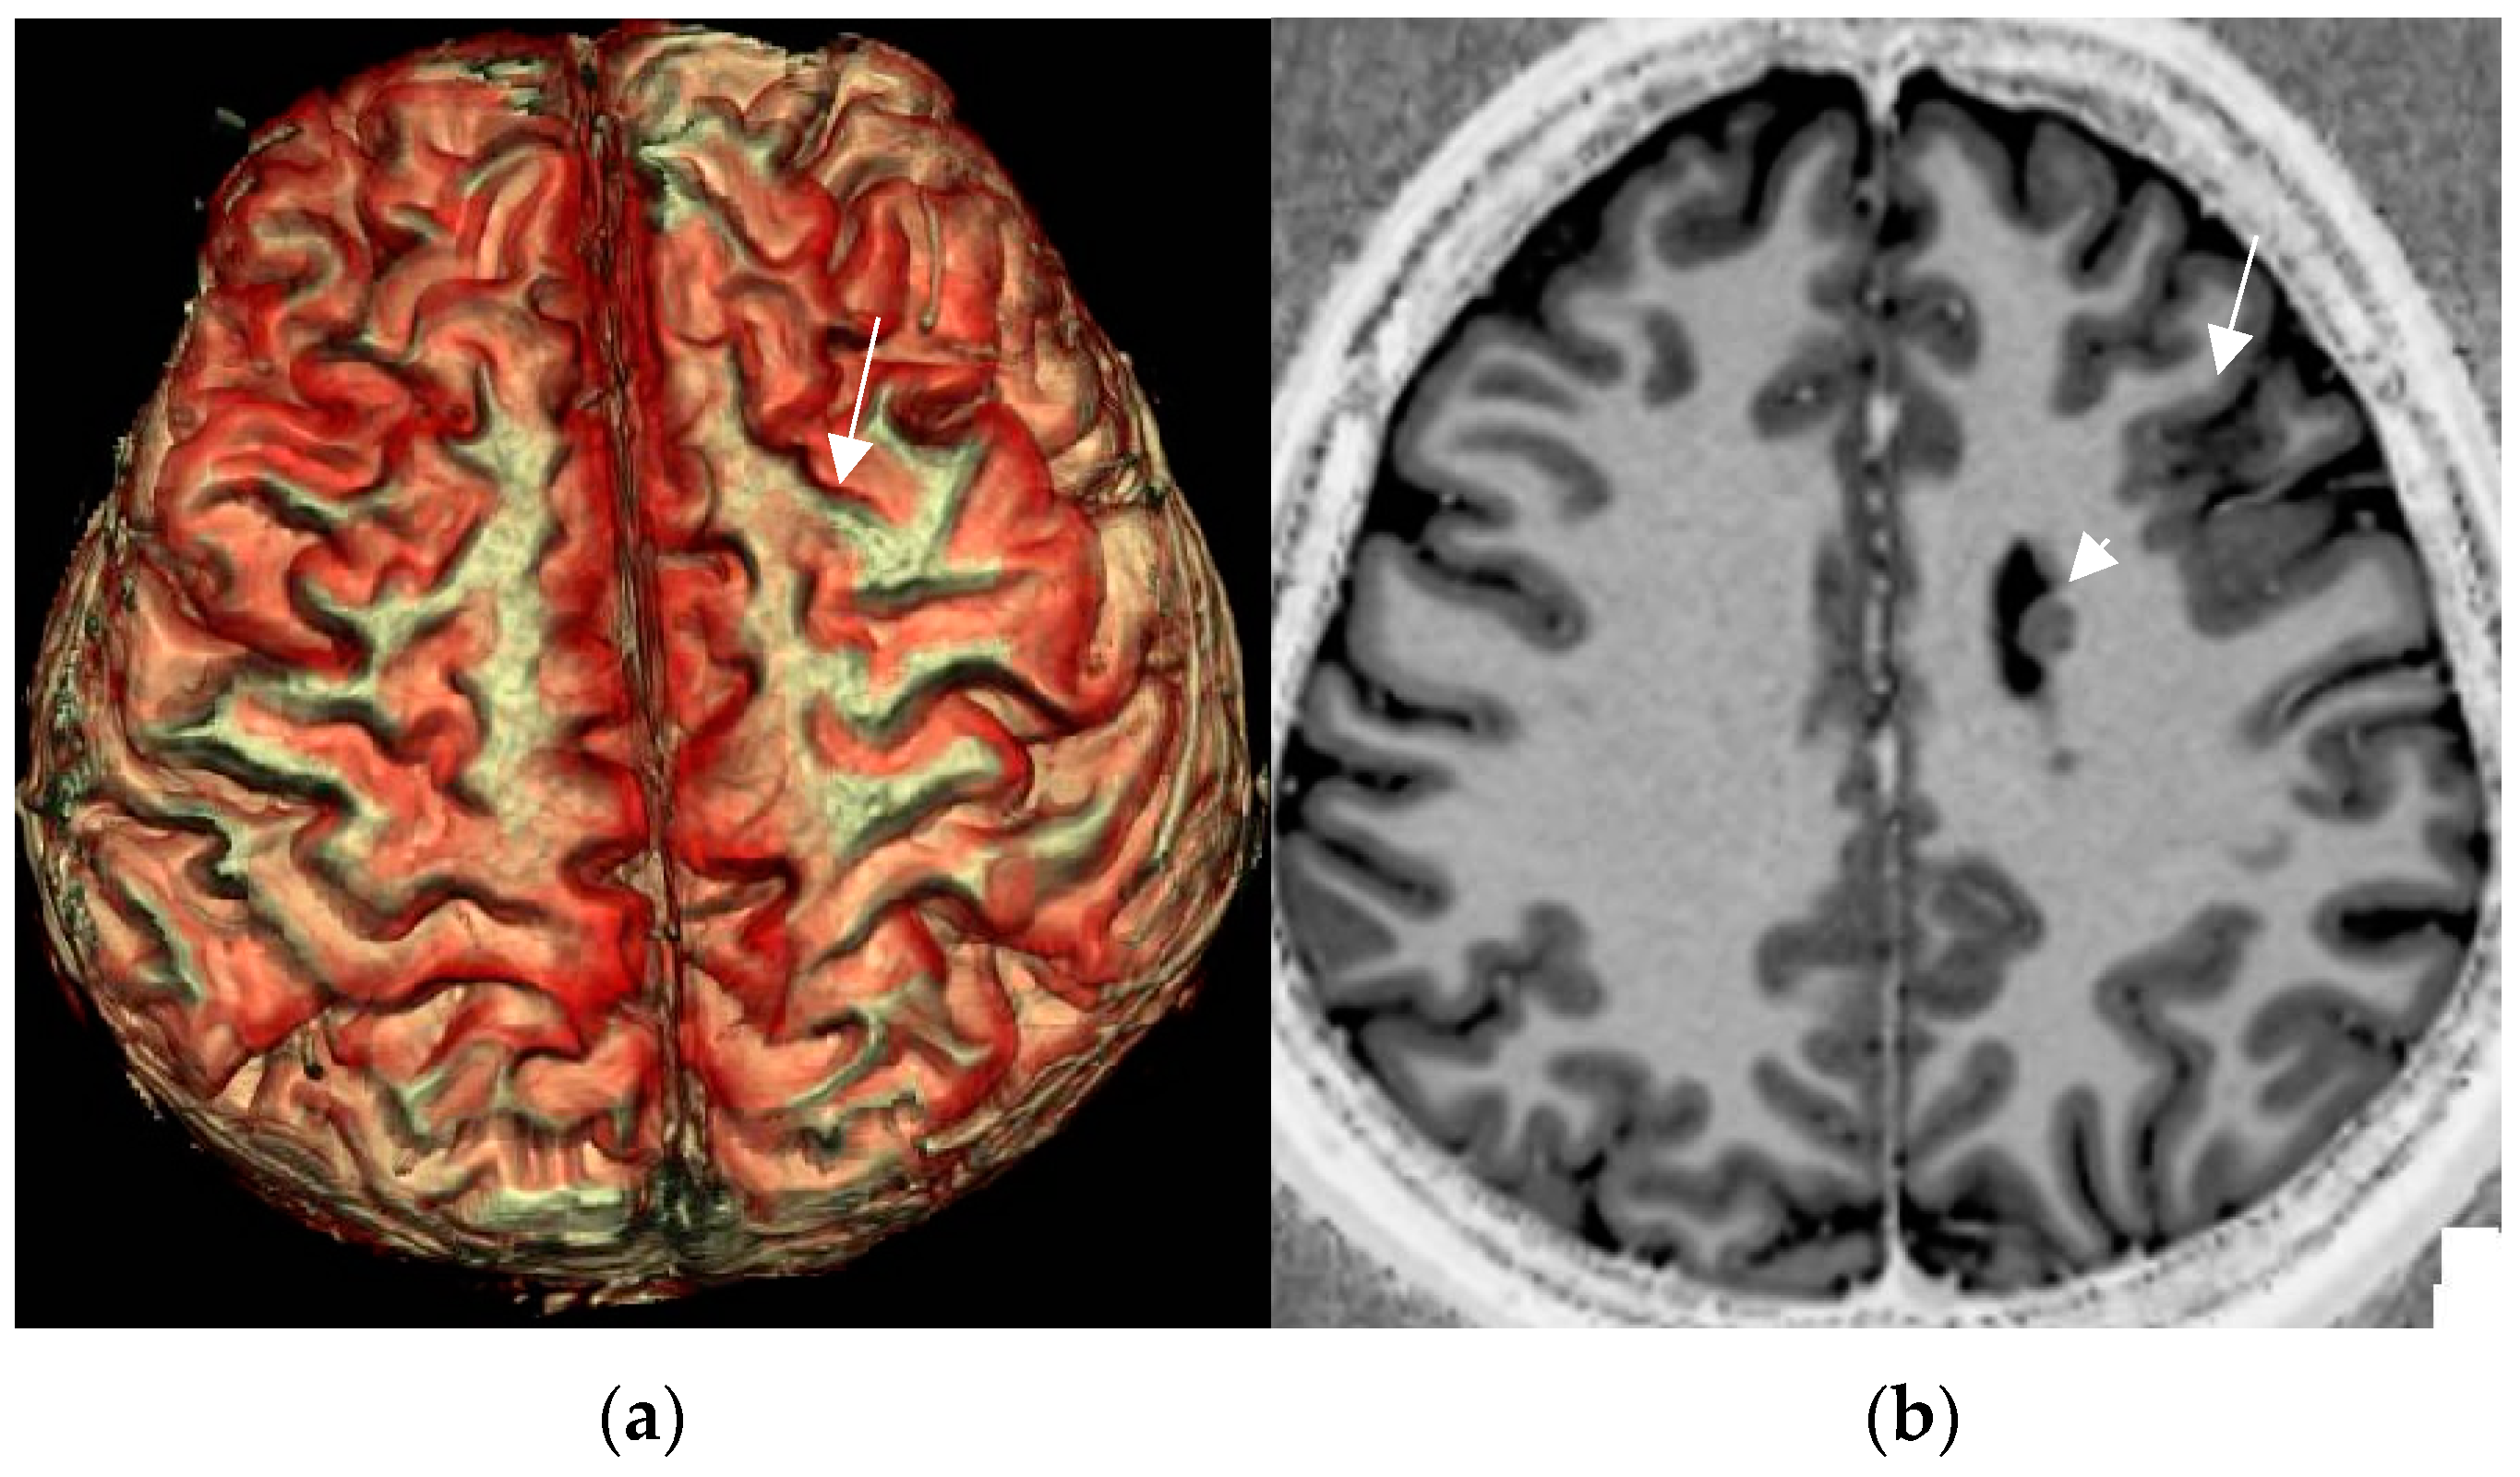

A practical tip is to increase the spatial resolution in a 3T field magnet by lowering slice thickness from 3 mm to 2–1.5 mm for T2 sequences while maintaining signal intensity. This is enabled by application of a head coil with a high number of receive coils—e.g., 64 channels in a 3T field system (Figure 3). Sensitivity for lesion detection is thus increased from 53.1% to 85.9% [72]. The most common pathologies additionally encountered in this study were FCD, nonspecific gliosis, and oligodendrogliosis.

Figure 3.

Mild malformation of cortical development along left central sulcus hardly depicted by slight cortical blurring and subcortical gliotic foci on 1.7 mm coronal T2 w image (arrow in (a)) (a). Improved visualization of the mMCD on sagittal (b) and coronal (c) MP2RAGE sequence (0.9 mm) with slight nodular irregularity of both cortical borders and focal subcortical extension (c).

Progressive substitution of 2D acquisition with 3D acquisition and thus lowering the slice thickness from 2–3 mm slice to 0.9–1 mm (=submillimetric) is a considerable yield-gaining strategy. This not only increases visual conspicuity for small lesions but moreover enables advanced postprocessing of 3D data.